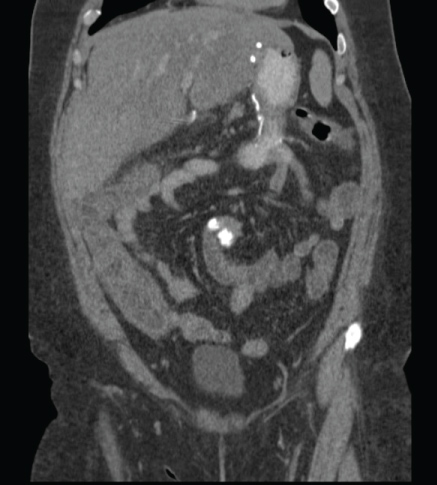

Patient #1 is a 52-year-old woman who had undergone a Silastic Ring Vertical Gastroplasty (SRVG) for morbid obesity in 1980, with an initial Body Mass Index (BMI) of 64.6 Kg/m². She lost 33 Kg during the first year after the operation, but since then her weight was stable with no further reduction. In 1998 she underwent an open cholecystectomy. With a BMI of 52.6 Kg/m², she was referred to our department for a revisional bariatric operation. Laboratory test results taken preoperatively, at readmission, and at discharge, are shown in Table 1. She underwent an uneventful laparoscopic BPD. Some intraoperative measures are shown in Table 1. The early post-operative period was unremarkable. Some post-operative parameters are also shown in Table 1. Seven weeks after the operation she started to complain of vague right abdominal pain and watery diarrhea and was ultimately diagnosed with colitis of the hepatic flexure and proximal transverse colon, based on computerized tomography (CT) (Figure 1). Her laboratory tests were as shown in Table 1. Stool cultures were negative for Salmonella, Shigella, Campylobacter Jejuni, and common parasites routinely examined in our hospital. The stool was also negative for Clostridium Difficile toxins A and B. She was treated with intravenous empiric antibiotics, resulting in a quick clinical and laboratory improvement (Table 1). Six weeks after her discharge, a colonoscopy was performed, demonstrating a normal mucosa throughout the colon, with no signs of inflammation or any other pathology. Random biopsies taken from hepatic flexure mucosa were normal. Since that event, she reported no other attacks of abdominal pain, diarrhea, or any other complaints.

Figure 1: CT scan of patient #1, showing colitis of the hepatic flexure and proximal transverse colon. View Figure 1